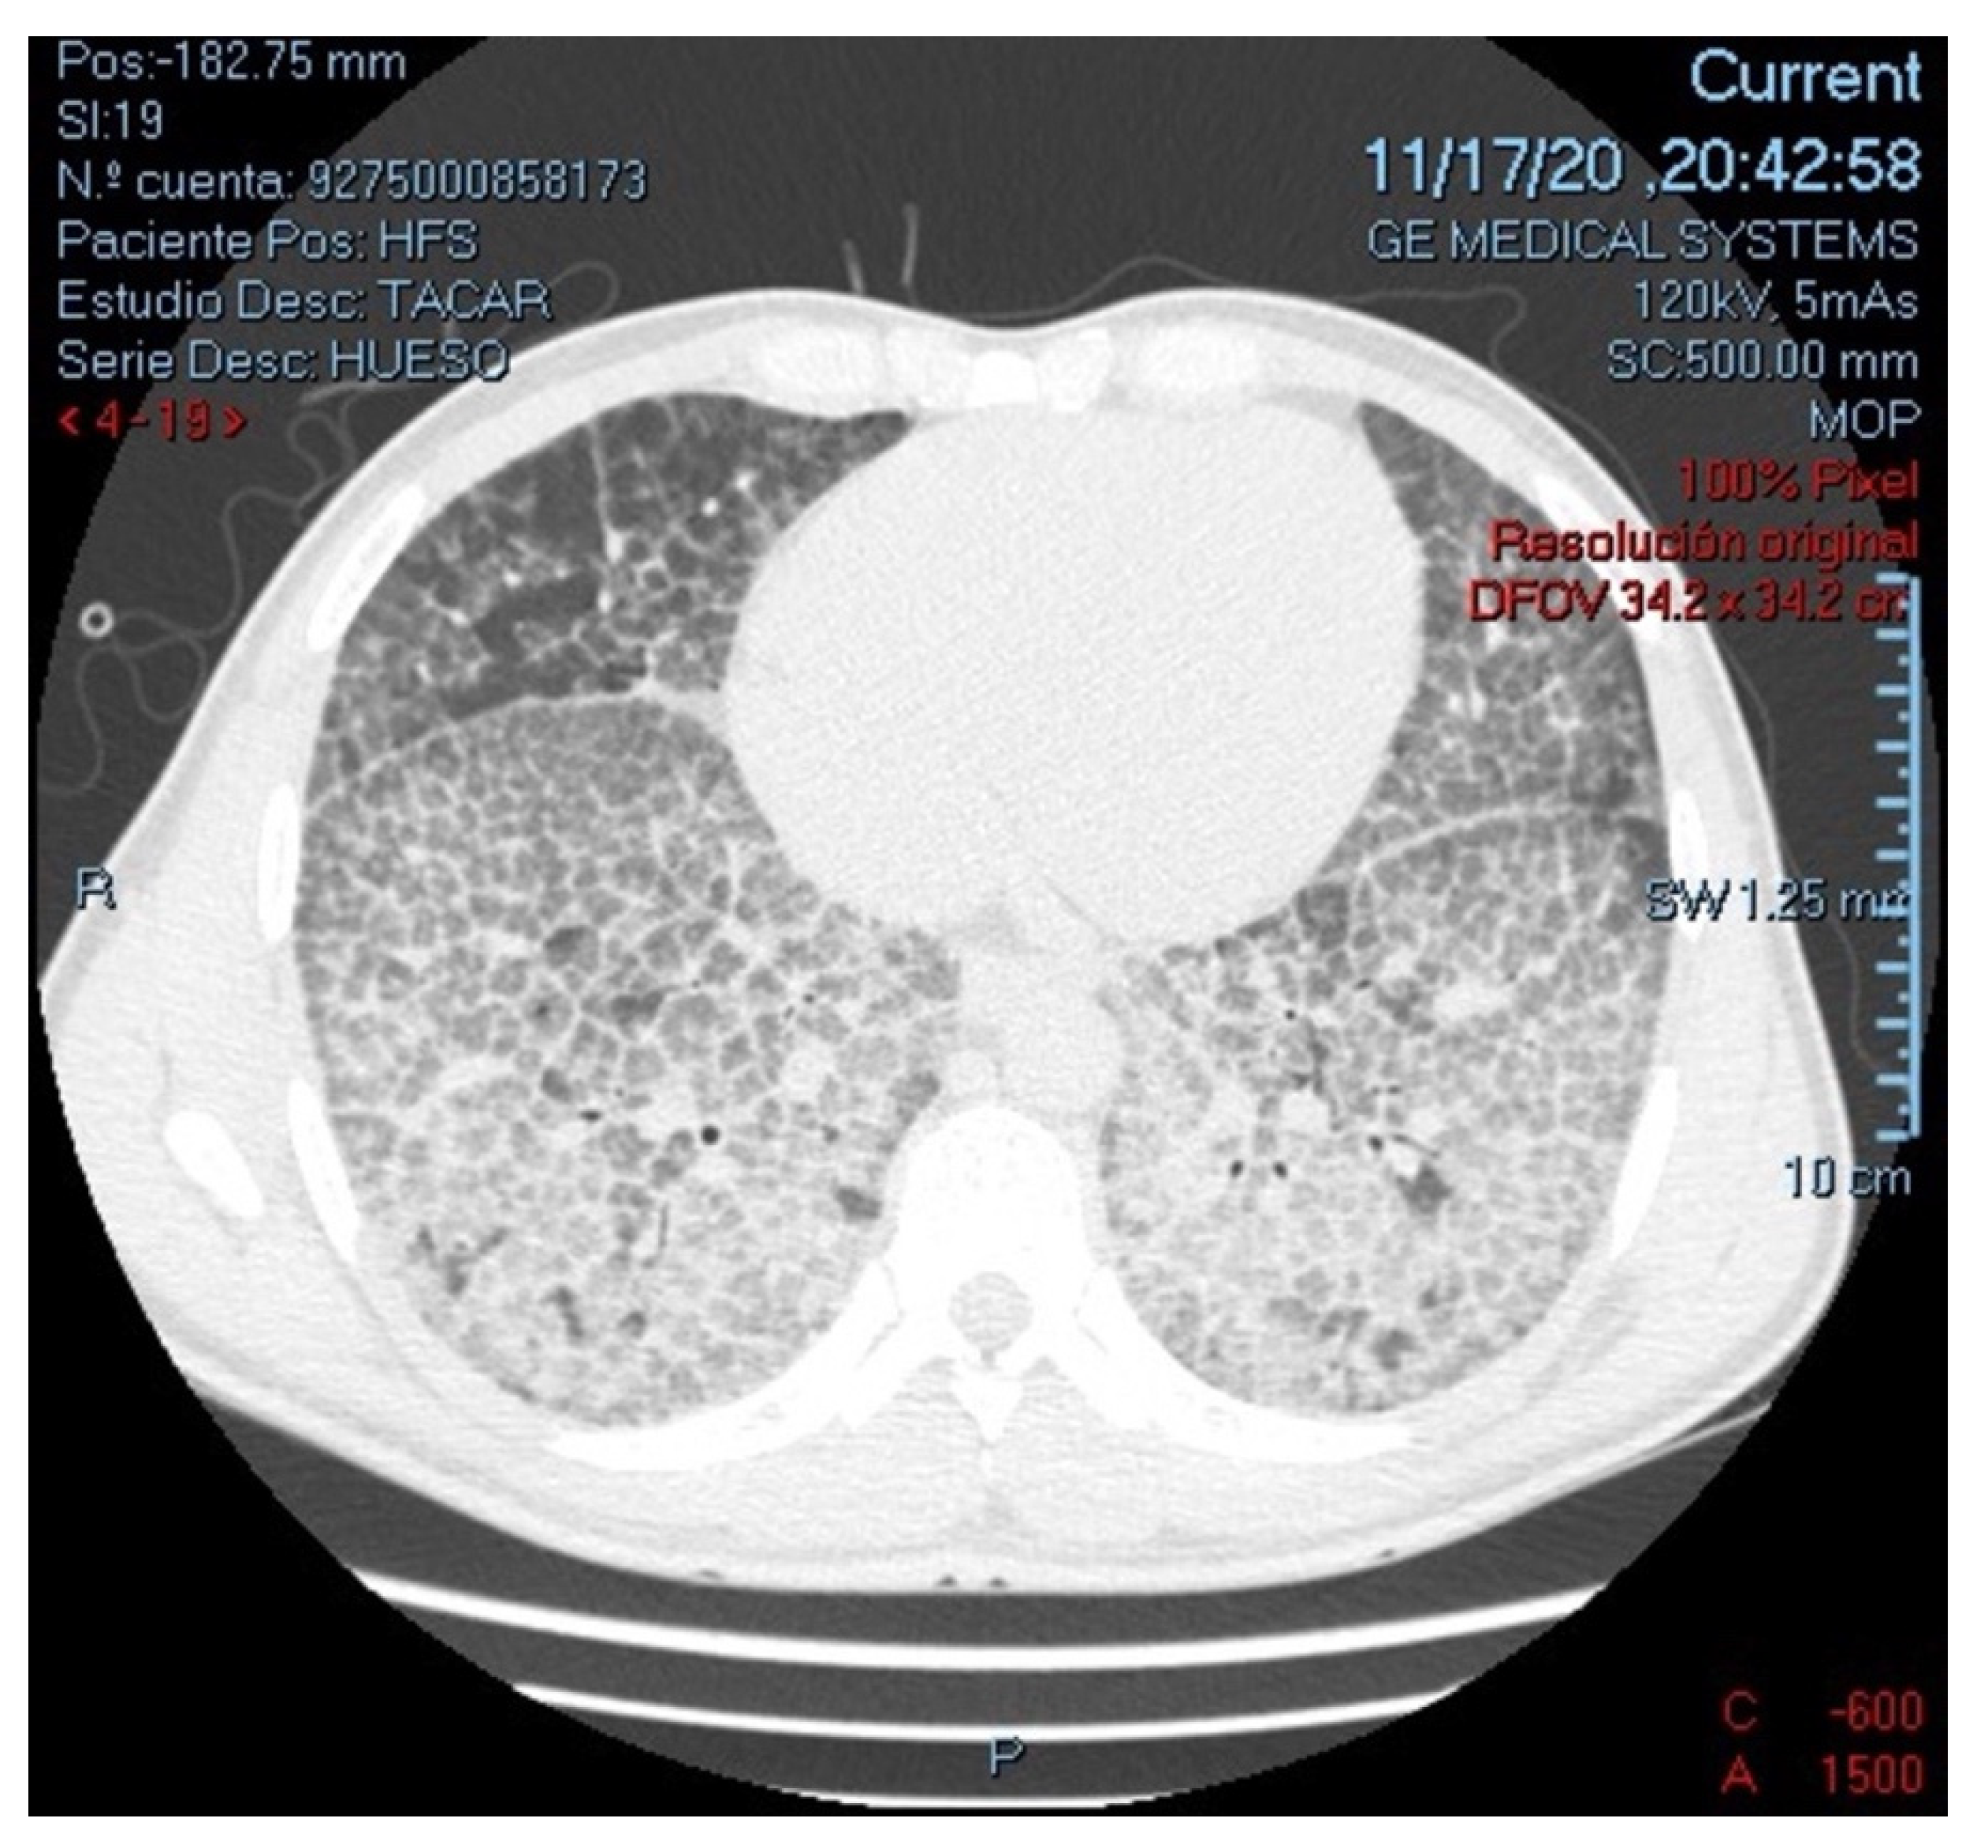

Alveolar Proteinosis Secondary to M. tuberculosis, in a Patient with Transient CD4 Lymphocytopenia Due to Cryptococcus neoformans Infection: First Case in the Literature

2. Case Report